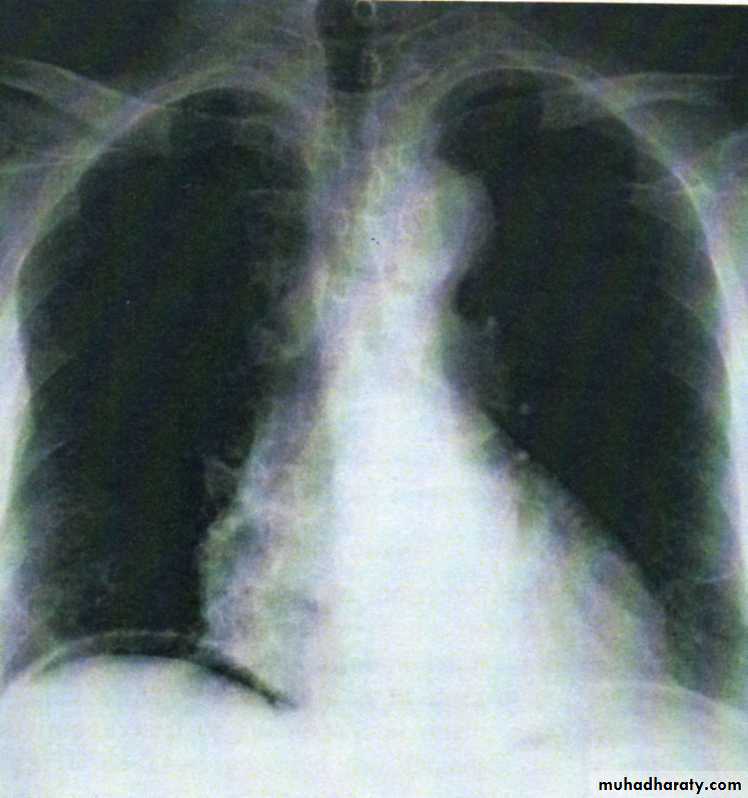

• A radiograph of the abdomen may confirm the presence of dilated gas-filled loops of bowel ( consistent with a paralytic ileus) or show free gas, although the latter is best shown on an erect chest radiograph . If the patient is too ill for an “erect” film to demonstrate free air under the diaphragm, a lateral decubitus film is just as useful, showing gas beneath the abdominal wall.

• Erect chest radiographs may show free peritoneal gas (perforated viscus).